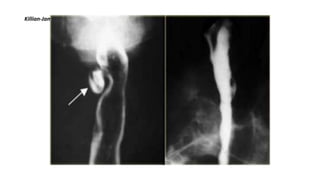

KILLIAN JAMIESON DIVERTICULUM

• Killian-Jamieson diverticulum is a pulsion diverticulum, that protrudes through a lateral anatomic

weak site of the cervical esophagus below the cricopharyngeus muscle. AP view shows

diverticulum (arrow) originating laterally.

• Lateral view confirms diverticulum does not originate posteriorly as a Zenkers diverticulum would.

Killian-Jamieson diverticulum: AP and lateral view